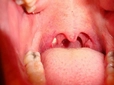

Bademcik İltihabı Nedir?Bademcik iltihabı, bademciklerin (tonsiller) iltihaplanması durumu olarak tanımlanır. Genellikle viral veya bakteriyel enfeksiyonlardan kaynaklanır ve boğazda ağrı, yutkunma güçlüğü ve ateş gibi belirtilerle kendini gösterir. Bademcikler, vücudun bağışıklık sisteminin bir parçası olarak görev yapar ve enfeksiyonlarla savaşmada önemli bir rol oynar. Ancak, aşırı enfeksiyon durumlarında iltihaplanabilirler. Bademcik İltihabının BelirtileriBademcik iltihabı, çeşitli belirtilerle kendini gösterebilir. Bu belirtiler arasında: